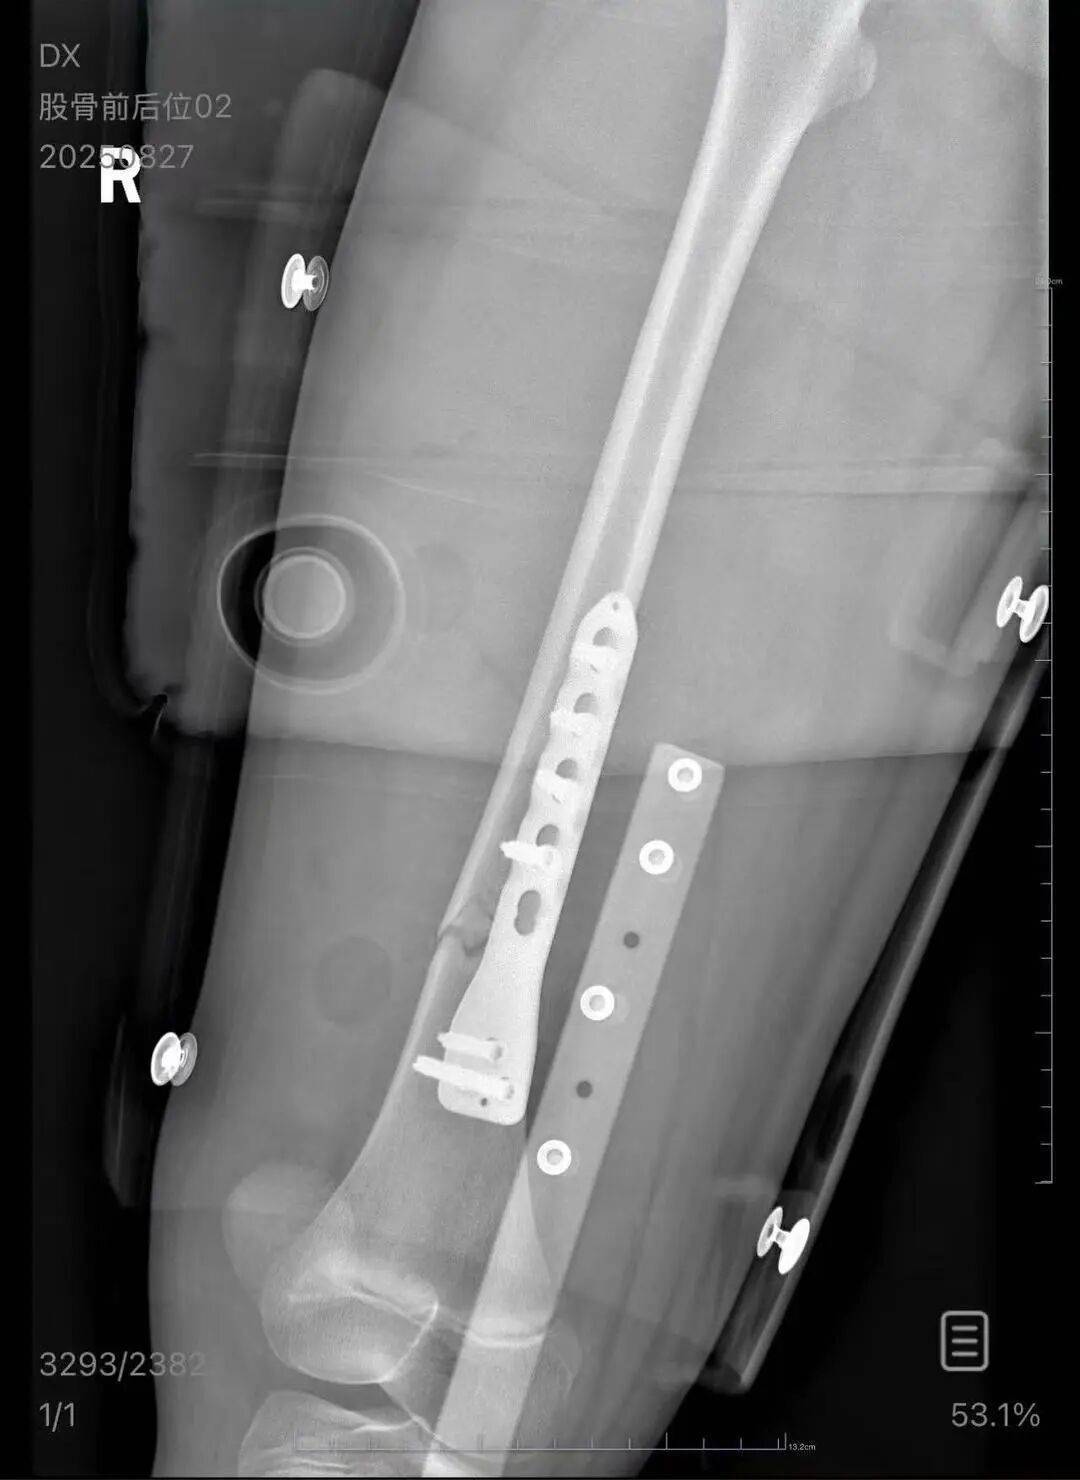

▲朱女士女儿手术后拍的X光片 受访者供图

朱女士向记者出示的医院病历显示,8月24日凌晨,朱女士的女儿到医院就诊XRP交易所。医院诊断朱女士的女儿右股骨骨折,需要住院进一步治疗。